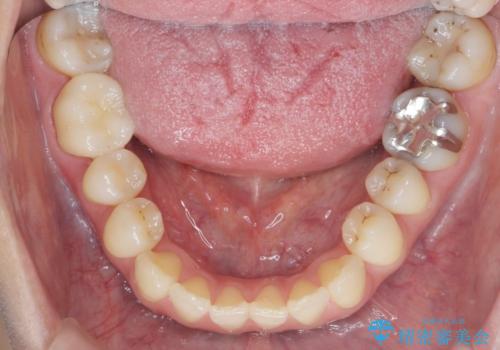

銀歯をゼロに! 短期間で行うメタルフリー治療

- 口の中に見える銀歯を、金属アレルギーの対策と審美性の向上のため全て除去したい!と希望され来院されました。

銀歯を丁寧に除去したのち、精度の良いセラミックインレー、セラミッククラウンで修復・補綴処置を行っていきます。

- 62.7万円(ジルコニアクラウン×3・仮歯×3・セラミックインレー×3)費用は治療当時の料金となります